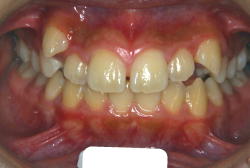

初診時の状態ですが、前歯の噛み合わせが逆転していて、下の前歯が外側に来て、上の前歯が裏側になっています。口元の様子ですが、前歯の重なり方が逆なので、唇の様子もそれを反映して、下唇が突出しています。反対咬合としてはかなり重症です。

分析してみると歯の傾き方に問題があるだけでなく、顎の骨の大きさと形にも問題があることが分かりました。ただし、骨の問題点が見つかったからと言って、必ずしも外科矯正になるわけではなく、このくらいの症状ですと、通常の矯正でもきれいに治すことができます。

診断の結果、下の前歯を正しい位置まで内側に入れていくためには、十分な隙間を確保することが避けられないと判断し、上の左右第二小臼歯と下の左右第一小臼歯は抜歯させて頂くことにしました。歯の本数は減りましたが、歯科医学的評価も大きく改善しましたし、審美的にも大幅な改善が見られますね。特に口元の様子が全然変わりました。